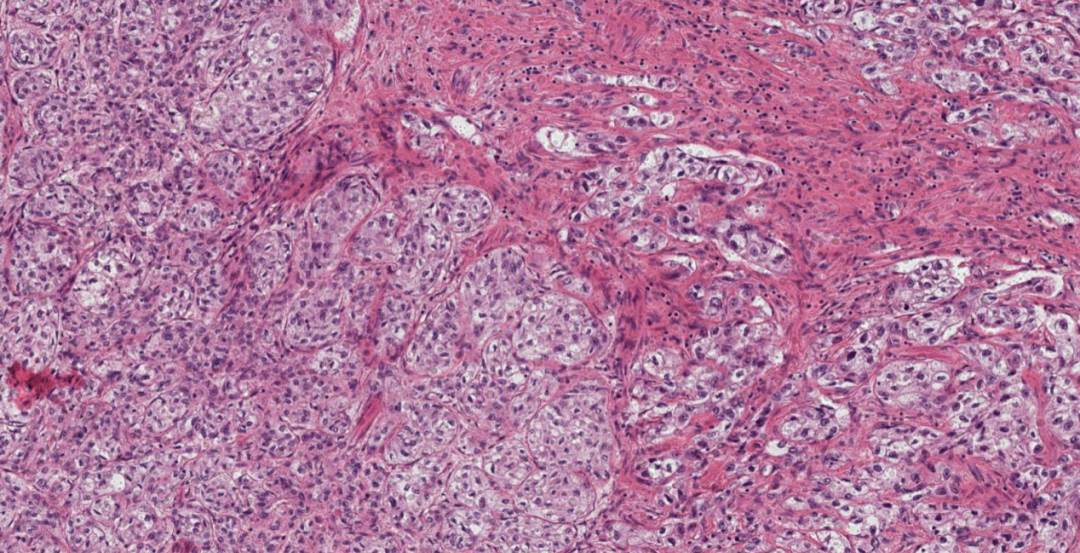

低倍镜下显示肿瘤富含血窦结构。

肿瘤细胞胞浆呈淡粉色,间质中可见丰富的纤细纤维血管束。

肿瘤细胞核形态为圆形或卵圆形,异型性不明显,核染色深,未观察到明显核仁。

- 部位: 膀胱PGL常位于黏膜下,有助于与起源于黏膜表面的尿路上皮病变鉴别。

- 生长模式: 典型的PGL呈现“Zellballen”(细胞球)样巢状结构,肿瘤细胞巢被纤细的毛细血管网分隔,巢周可见支持细胞。

- 细胞特点: 肿瘤细胞通常胞浆嗜酸性,核呈圆形或卵圆形。少数情况下可见核多形性或深染,需与尿路上皮癌、前列腺癌或肾细胞癌鉴别。

- 间质特点: 间质富含纤细的毛细血管网,支持细胞围绕在肿瘤细胞巢周围。